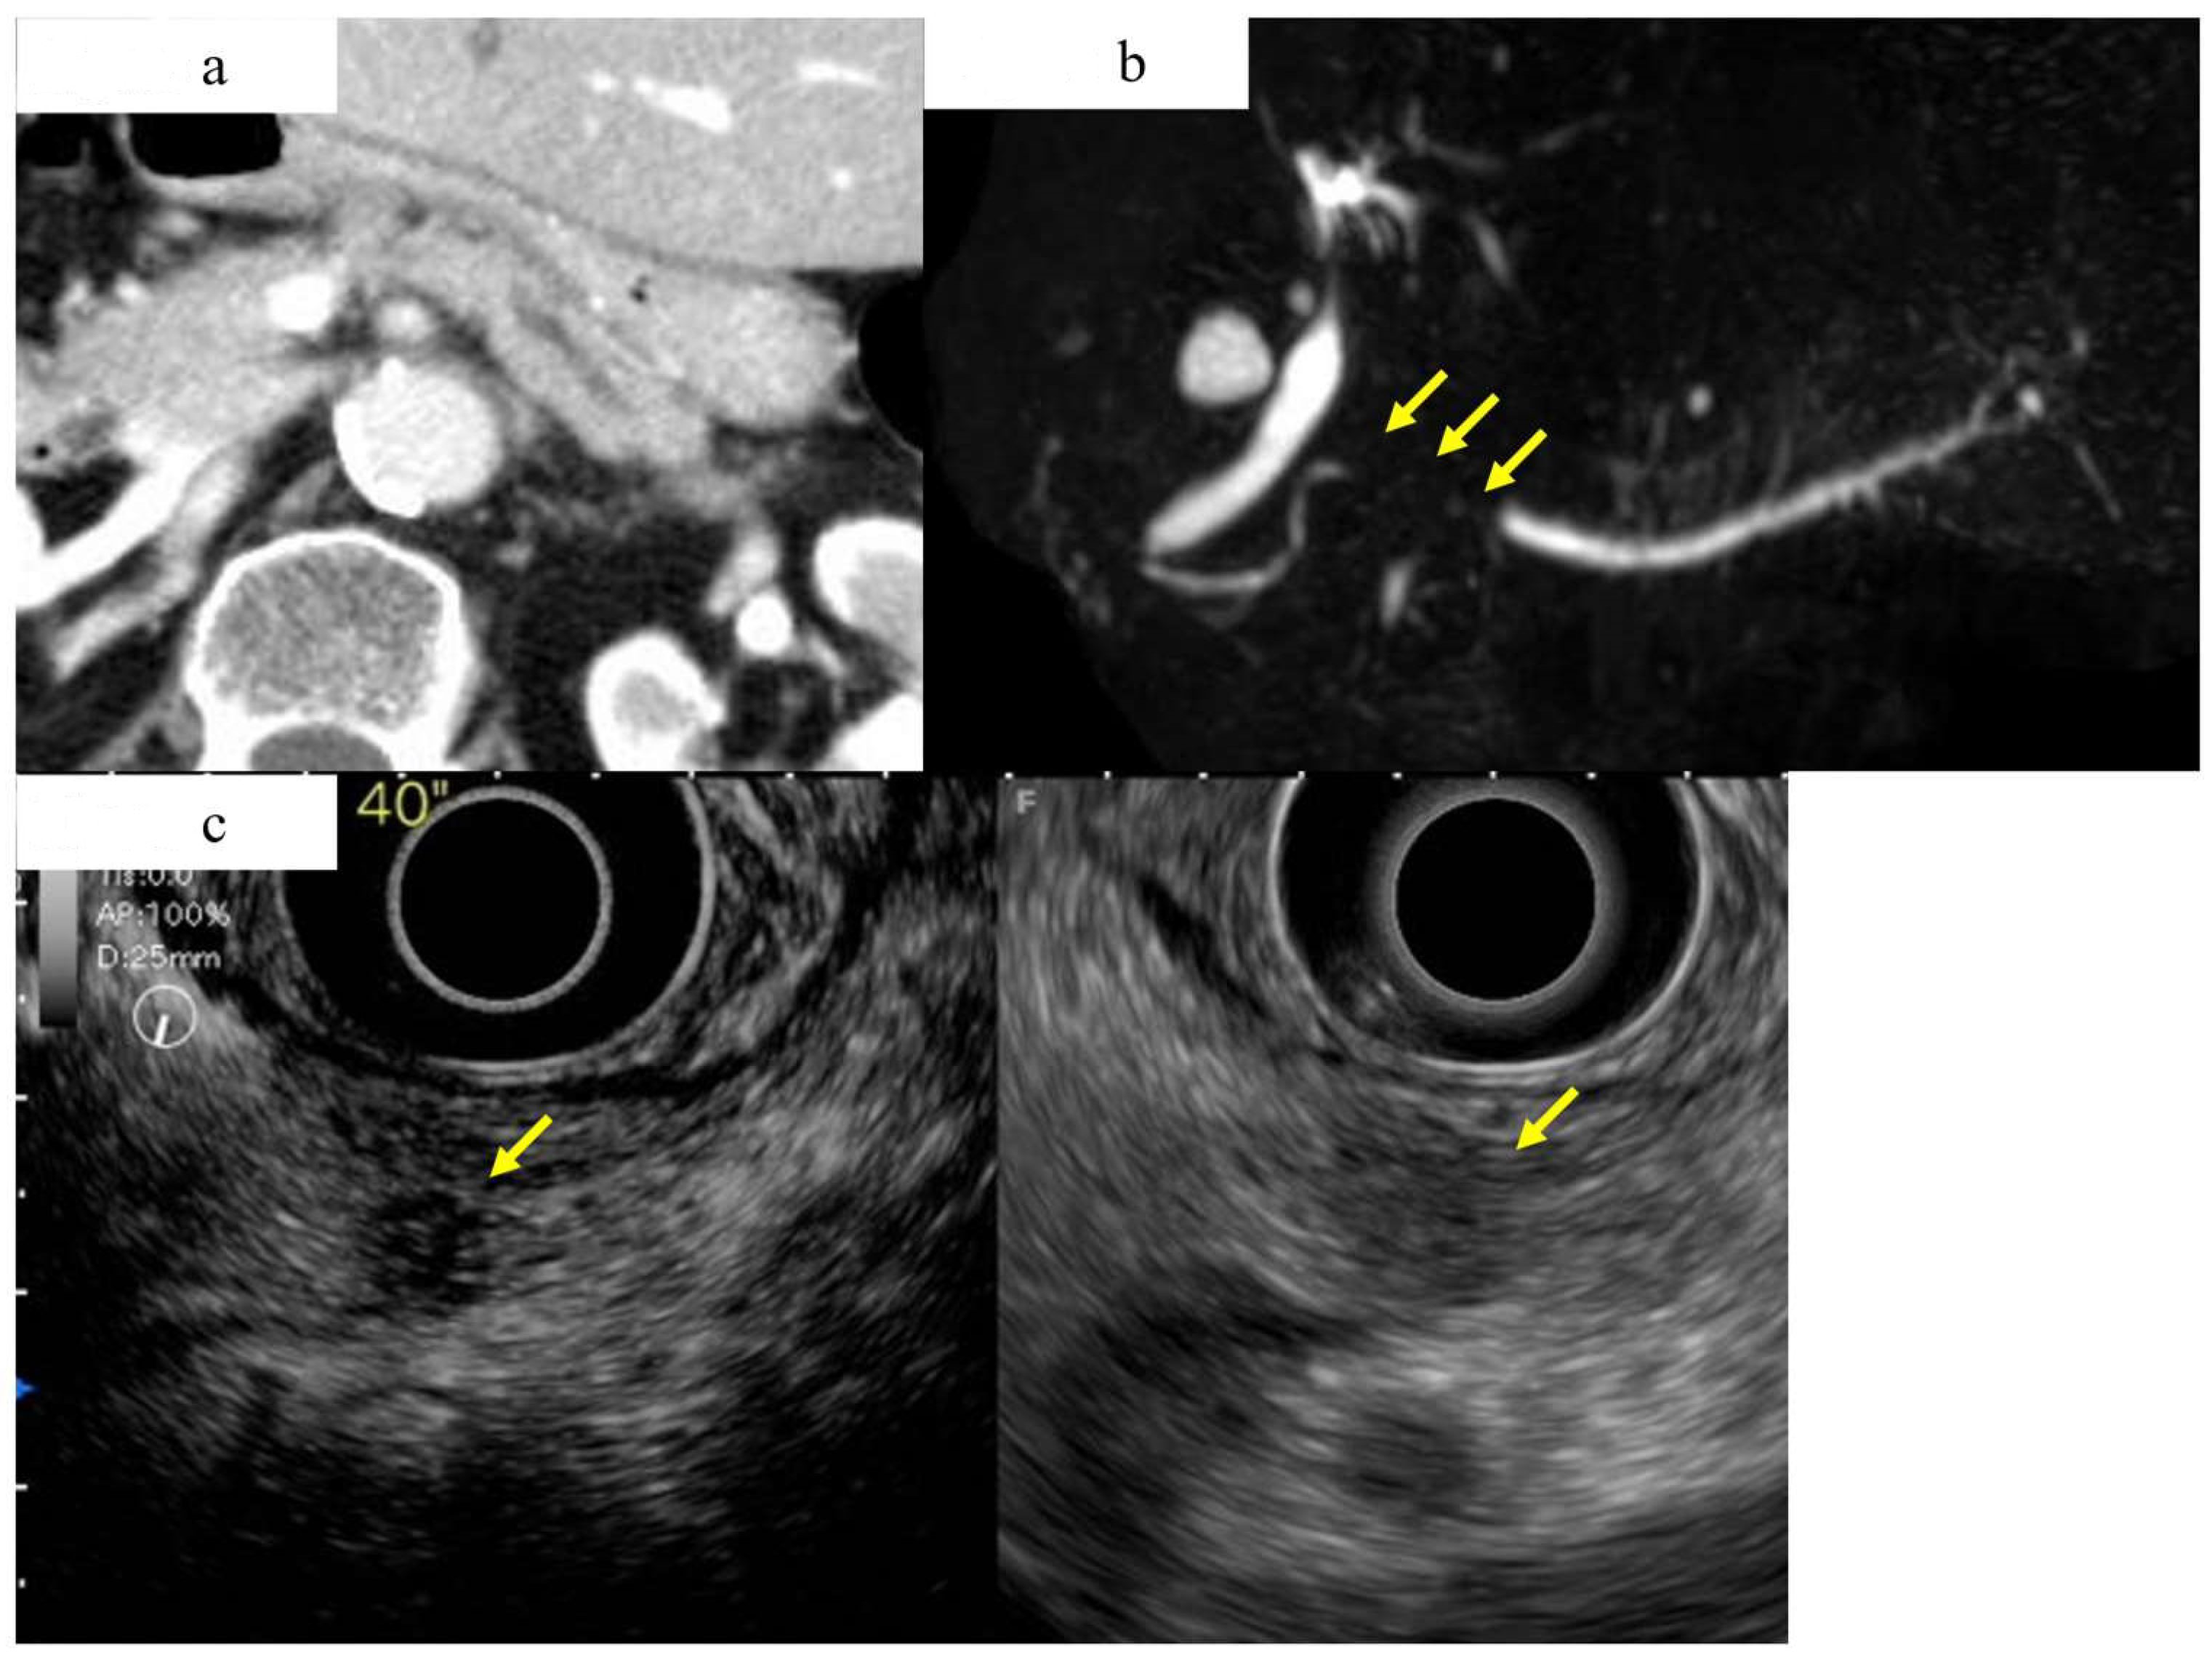

Figure 4.

A case of intraepithelial carcinoma of the pancreas, early-stage PDAC, in which no pancreatic tumor was found by CT or MRI imaging, but severe lipidosis of the pancreatic body was observed, leading to the diagnosis of a pancreatic tumor by pancreatic fluid cytology. (a) Magnetic resonance cholangiopancreatography showing stenosis of the MPD (yellow arrow) and dilation of the MPD and branch ducts in the caudal part. (b) Enhanced CT showing localized atrophic change (yellow arrow) in the pancreatic body and dilation of the MPD in the caudal part. (c) Endoscopic retrograde cholangiography demonstrating stenosis of the MPD in the pancreatic body (yellow arrow) and detailed in the caudal part. (d) In the resected specimens, severe stenosis of the main pancreatic duct was observed in the resected sections 2–8 (yellow frame), and, in particular, severe steatosis was observed in the resected sections 2–11 (out of the blue frames, 4 and 4). Additionally, 5 shows the resected section. High-grade PanIN was detected in the 4, 5, and 6 resected sections of the pancreatic body (red frame). (e) Pathological findings indicated the low papillary proliferation of the pancreatic duct epithelium in the lumen of the main pancreatic duct of pancreatic bodies 4, 5, and 6 and pancreatic lobules associated with chronic pancreatitis in the surrounding pancreatic tissue. Disappearance, fatification, and remaining islets of Langerhans were observed (HE × 40). The pancreatic ductal epithelium exhibited nucleomegaly, a mild chromatin increase, and some clear nucleoli, and high-grade PanIN was detected (HE × 100).